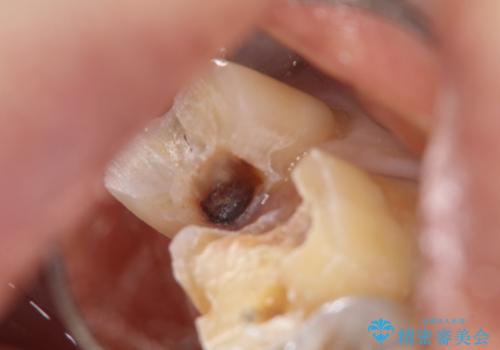

銀歯を外すとかなり大きな虫歯になっていました。幸いぎりぎりのところで神経まで虫歯は広がっていなかったため、症状が出ない事を確認した後、オールセラミッククラウンで治療しました。虫歯除去後、残っている歯質が少なかったため、破折抵抗を考慮し部分的な被せ物ではなくクラウンを選択しました。

※被せ物では歯と被せ物の適合がとても大切になります。適合が悪い被せもの(歯と被せものの間に隙間がある)を入れるとそこに汚れが溜り虫歯の原因となります。当院では精度が高い被せものを追求するため、サージテル(拡大鏡)や型取りの材料にシリコン材を使用しています。